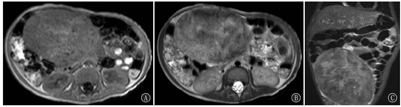

在MRI上,2例病灶周围呈T1WI及T2WI等信号,中心呈斑片样或结节样T1WI及T2WI高信号(图3),1例病变T1WI上呈周围等信号,中心高信号,T2WI上呈周围高信号,中心更高信号。弥散加权成像(DWI)(b=800 s/mm2)上病灶周边部分呈高信号且增强后强化明显,中心部分弥散不受限,增强后不强化或仅轻微强化(图4)。3例病变内均观察到迂曲流空血管影。1例腹壁及右髂窝多发结节灶(图5)、1例腹股沟区多发肿大淋巴结亦可见弥散受限及明显较均匀强化。

在MRI平扫图像上,本组肿瘤多数呈现出"内高外低"的信号特点:即T1WI上多数表现为中心高信号、周围等信号,T2WI上病灶周围呈等/高信号,中心呈高/更高信号,这可能与肿瘤中心部位的出血、坏死有关。高b值DWI上可见病灶周边部分弥散受限且增强后强化明显,中心部分弥散不受限,增强后不强化或仅轻微强化,这种"弥散与强化相对应"的表现可能提示肿瘤的外周部分肿瘤细胞排列密集或具有恶性潜能。1例腹壁及右髂窝多发结节灶、1例腹股沟区多发肿大淋巴结亦可见弥散受限及明显较均匀强化,提示为恶性转移。3例病变内均观察到迂曲流空血管影,多以周围分布为主。